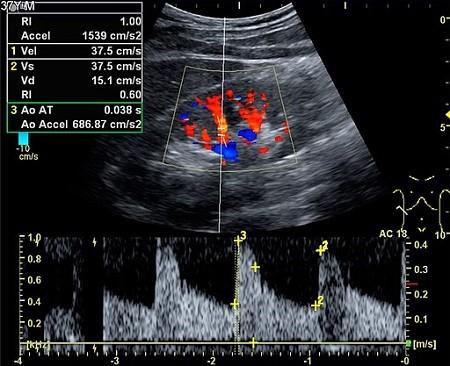

Les ondes sonores peuvent également être converties en images couleur sur un écran afin de visualiser le flux dans les artères ou les veines (Doppler couleur) - comme ci-dessous.

Echographie Doppler couleur

Par Mikael Häggström [CC0] (Travail personnel), via Wikimedia Commons

Ils peuvent également être représentés sur un graphique montrant les changements de vitesse et de direction (vélocité).

Les images ci-dessous sont produites à partir d'un scanner Doppler du rein.

Échographie rénale

Par Kristoffer Lindskov Hansen, Michael Bachmann Nielsen et Caroline Ewertsen [CC BY 4.0 (https://creativecommons.org/licenses/by/4.0)], via Wikimedia Commons